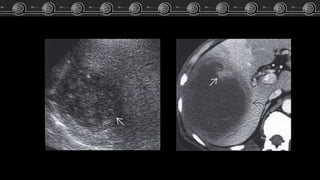

Adenoma, Hemangioma óHNF?? Caso Clínico Fem de 83 años…. El estudio TC demostró lesión focal a nivel del lóbulo izquierdo del higado. ARCHIVO DOCENTE DE TOMOGRAFÍA Y RESONANCIA C.M.C.